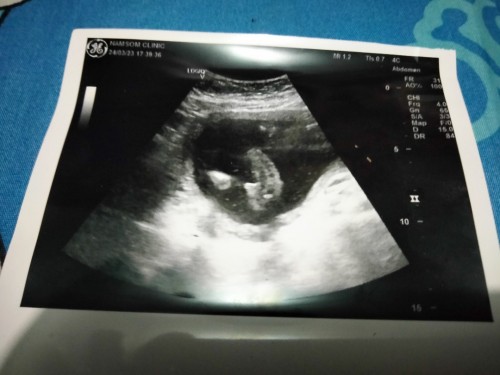

เบบี๋ในวัย 17 week นู๋เป็นเด็กผู้ชายนะครับ พ่อพ่อดีใจมา 😅🤰🏻👼🏻 ทีแรกลุงหมอบอกลูกสาวมาตรวจรอบนี้กระจู๋โผล่แล้วครับ 😂😂

ตอน17วีค หมอบอกผู้ชาย ล่าสุดซาวด์ 20วีค 5วัน ชัดเจนเลย กระจู๋โผล่มาเลย คุณพ่อดีใจมาก ลูกคนแรกเขาอยากได้ผู้ชาย

ยินดีด้วยค่ะ ขาชี้โชว์จู๋เหมือนลูกชายเราเลย เห็นตอนสัปดาห์ที่12 คลอดเดือนหน้าค่ะ ❤️❤️

มองยังไงค่ะแม่ๆ หมอบอกผู้ชาย แต่ภาพซาวทำไมไม่เหมือนคนอื่น😅🙏🏻

ยินดีด้วยนะคะ บ้านนี้ก้อลูกชายค่ะ 17Wตรวจรอบแรกก้อเจอจู๋เลยค่ะ☺️

บ้านนี่จู๋มาเต็มเลยค่ะ ซาว์ดเจอจู๋น้องตอน21วีคค่ะ